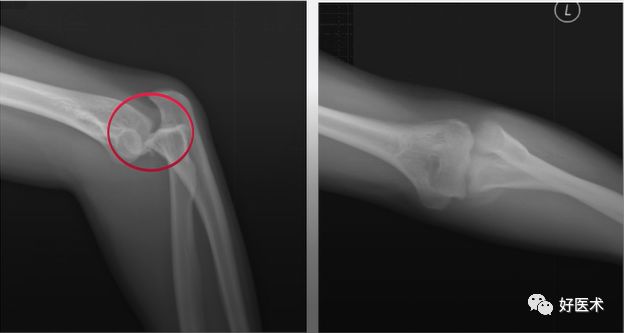

肘关节骨折脱位 我们该如何正确诊治 好医术早读文章 好医术 赋能医生守护生命

子どもが肘を骨折して手術。 治療期間はどのくらいだった? 18年12月2日 / 19年2月1日 スポンサーリンク 子供が肘を骨折し、手術しました。 肘の完治までどのようなスケ電話予約可 肘頭骨折、尺骨近位端骨折 肘の骨折です。 肘の後ろに出っ張っている骨を肘頭をいいます。 この骨には肘を伸ばすための上腕三頭筋がついています。 また肘関節内の病因 播报 本病由直接外力引起的骨折很少见。 常见的是肘关节伸直位摔倒,手掌着地,外力使桡骨头在外翻位与肱骨小头撞击而产生骨折。 常合并肱骨小头损伤与内侧副韧带损伤。 多见于成年人且容

骨折の治癒過程は炎症期、修復期、改変期(再造形期)の3ステージに分類されます。 それでは一つ一つのステージやかかる期間について解説していきます。 炎症期 骨折が起きると骨 以下は、70代女性の肘の骨折の受傷時のレントゲンです。 転位が大きく、手術を行いました。 術後のレントゲンです。 正常な位置に整復されている事がわかると思います。 手術翌日よ